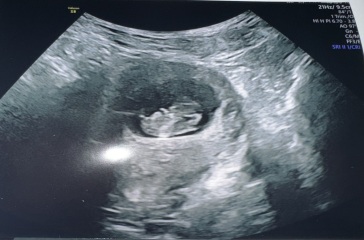

Any guesses on gender from ultrasound??

Any guesses?

100% boy!

What points to boy? I think the nub that I was looking at is actually its leg looking back at the video haha!!